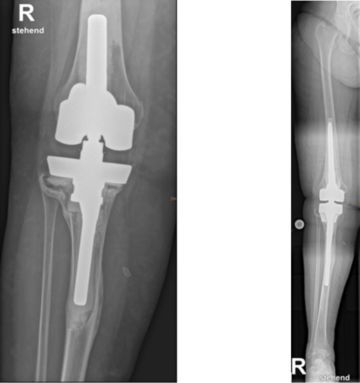

Gelockerte Knieprothese vor und nach Wechsel auf eine gekoppelte Knieprothese